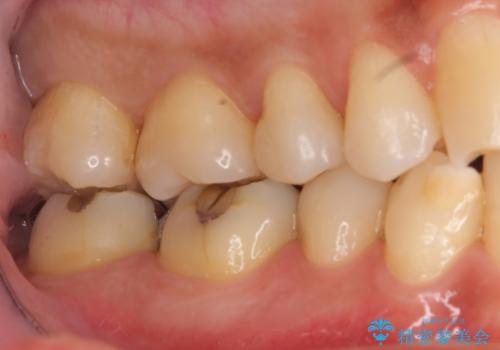

奥歯の虫歯 セラミックインレーに

- 上の奥の虫歯をセラミックインレーで修復しました。

治療前後の写真をお見せして説明したところ、非常に喜んでいただきました。

特に自費のインレーの適合(歯にぴったり合っている)はとても良く、虫歯になりにくいです。

高価なようで、実は将来のことを考えた歯を残す治療の第一歩です。